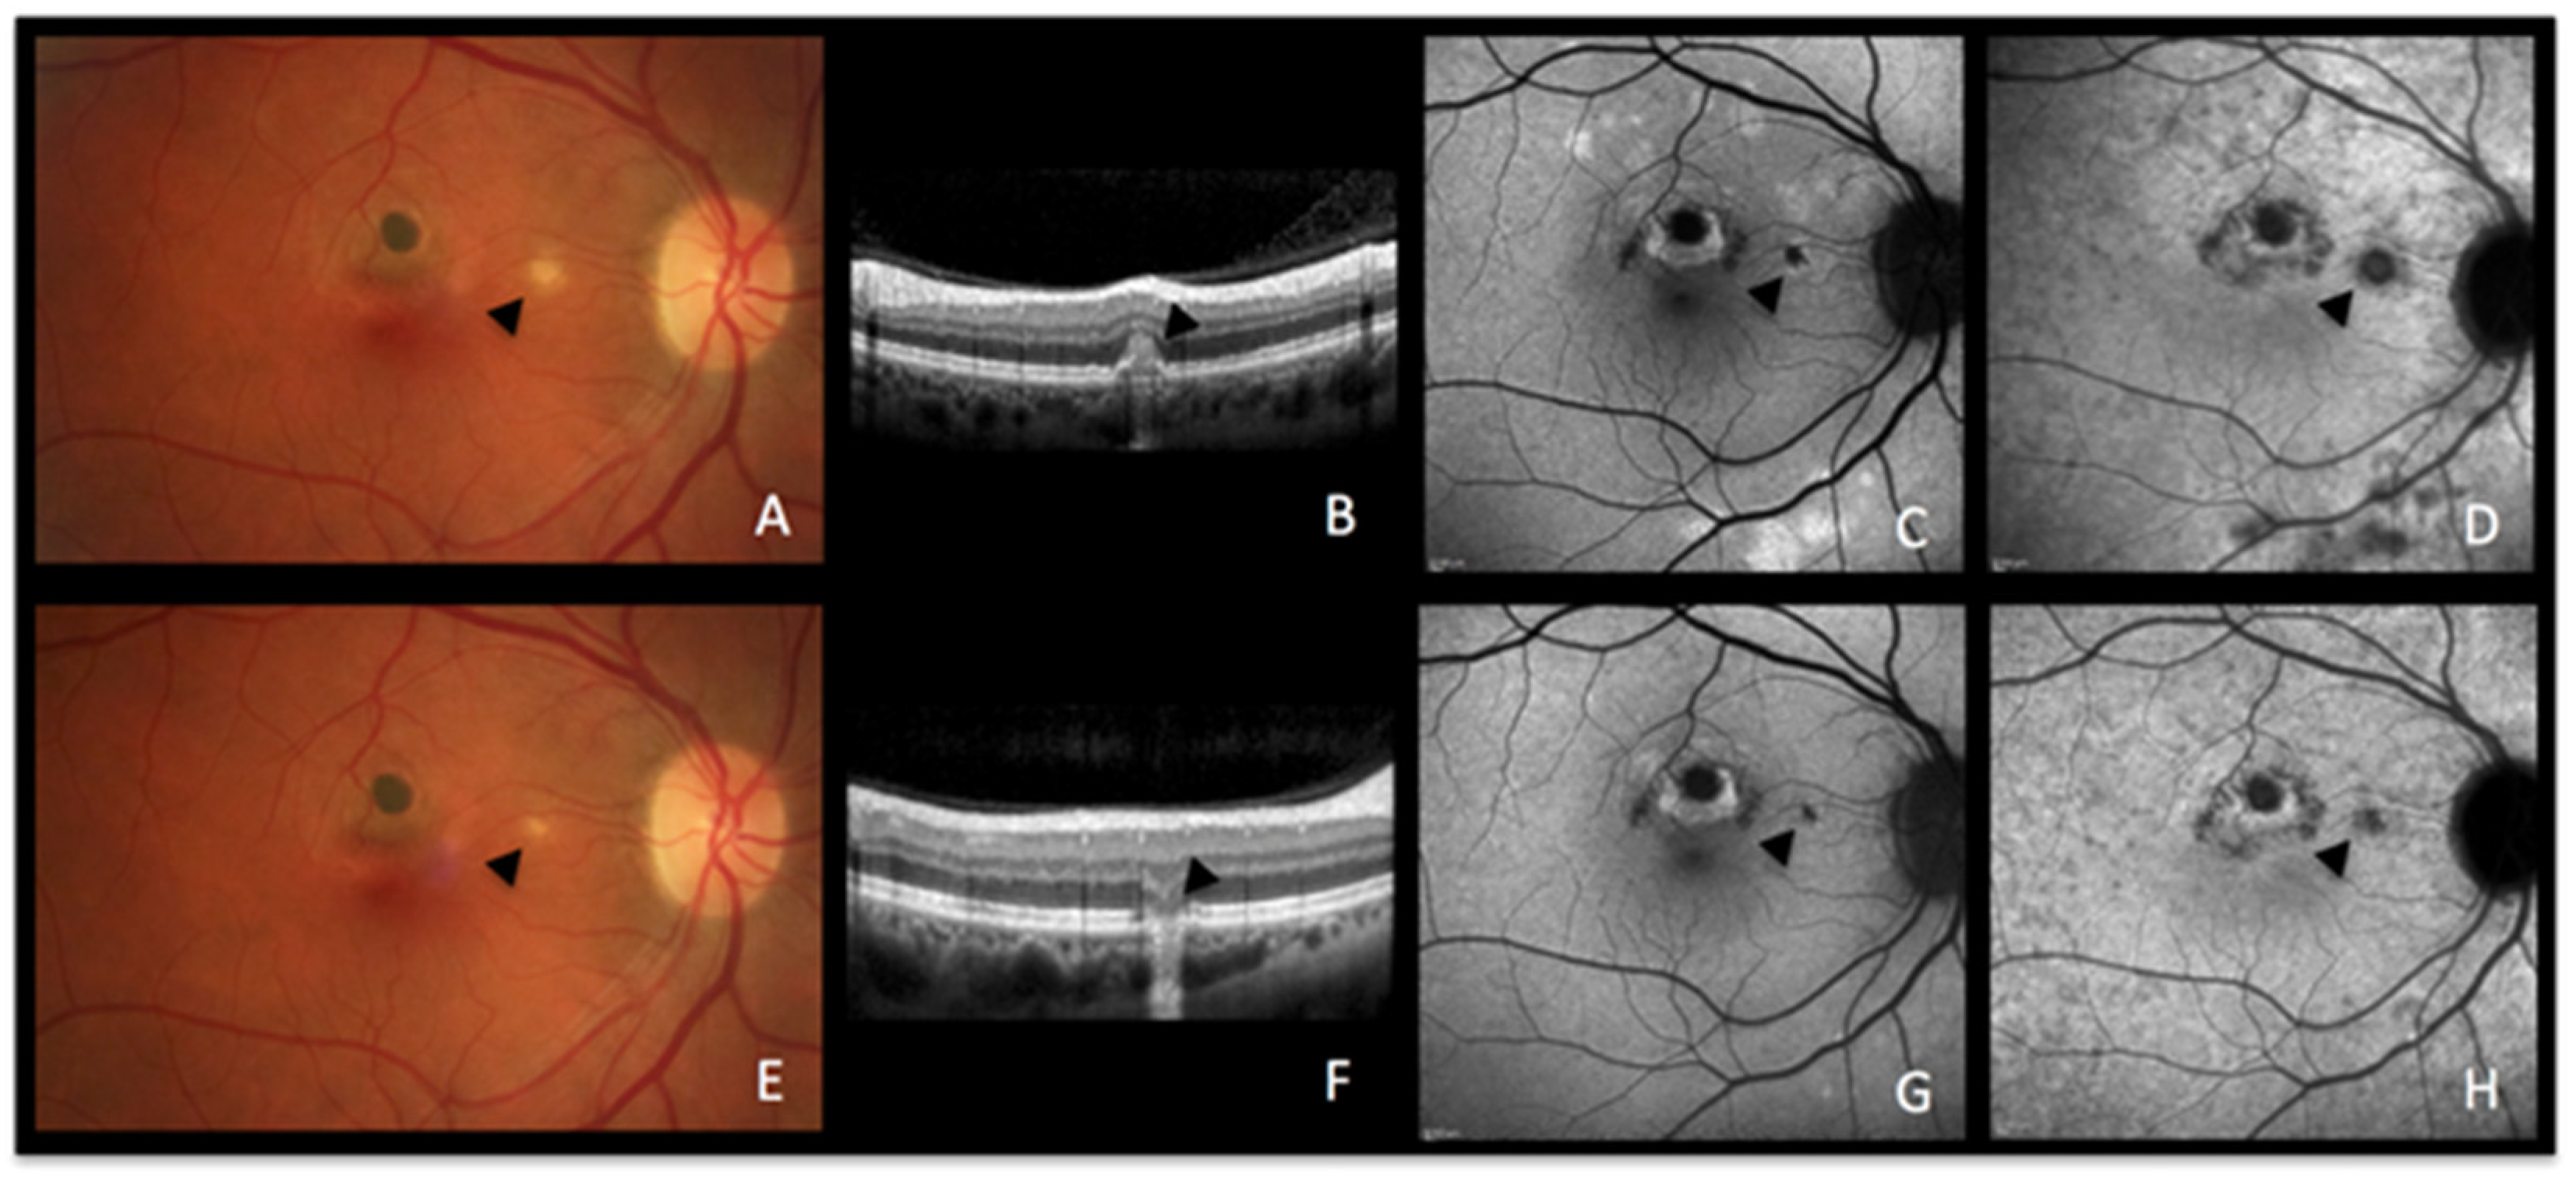

5.1. Acute Zonal Occult Outer Retinopathy (AZOOR) Figure 7

Case 6